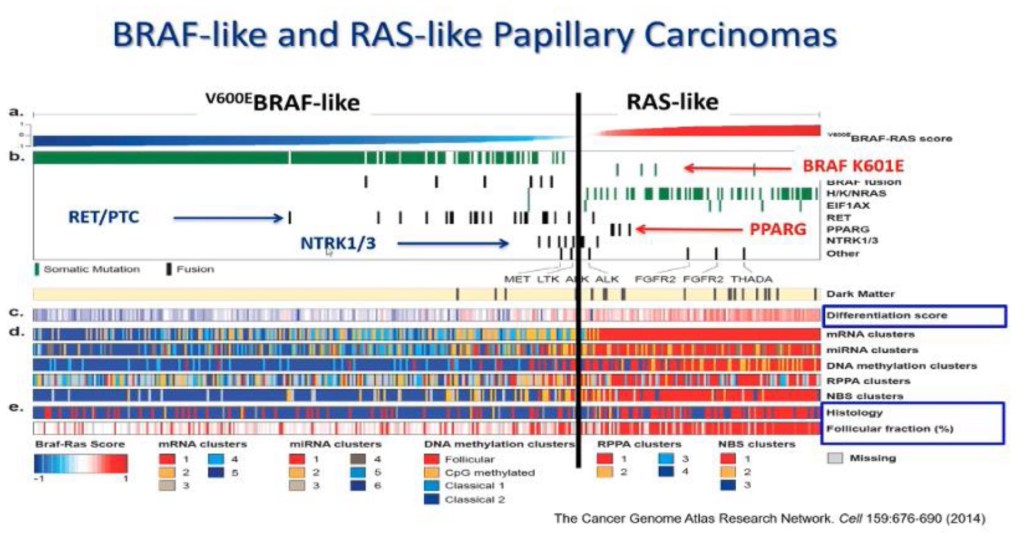

The RET proto-oncogene is located on chromosome 10. A genetic mutation in the RET oncogene is seen in all cells in the body in patients with the hereditary forms of MTC. Mutations in RET can also be seen only in the tumor cells in patients with sporadic MTC. Since the discovery of the RET oncogene, more than 100 different mutations have been identified in the gene in patients with MTC.